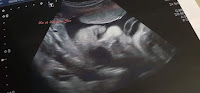

Le 2 juin , j'avais réalisé ma dernière échographie à environ 32 sem , un bébé jouflu qui était estimé à 2.1kg. (3.6 kg à terme). Le 3 juin, rdv du 8 mois+ anesthésiste ( qui est effectué à 8 mois maintenant et plus 9 mois comme précédemment) . Rdv nickel col fermé un peu déhiscent ! Elle m'a dit il faut tenir jusqu'à 36sa !